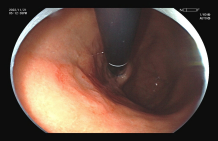

图示:放大胃镜下早期胃癌的微结构排列紊乱,微血管呈现扭曲、形态不规则